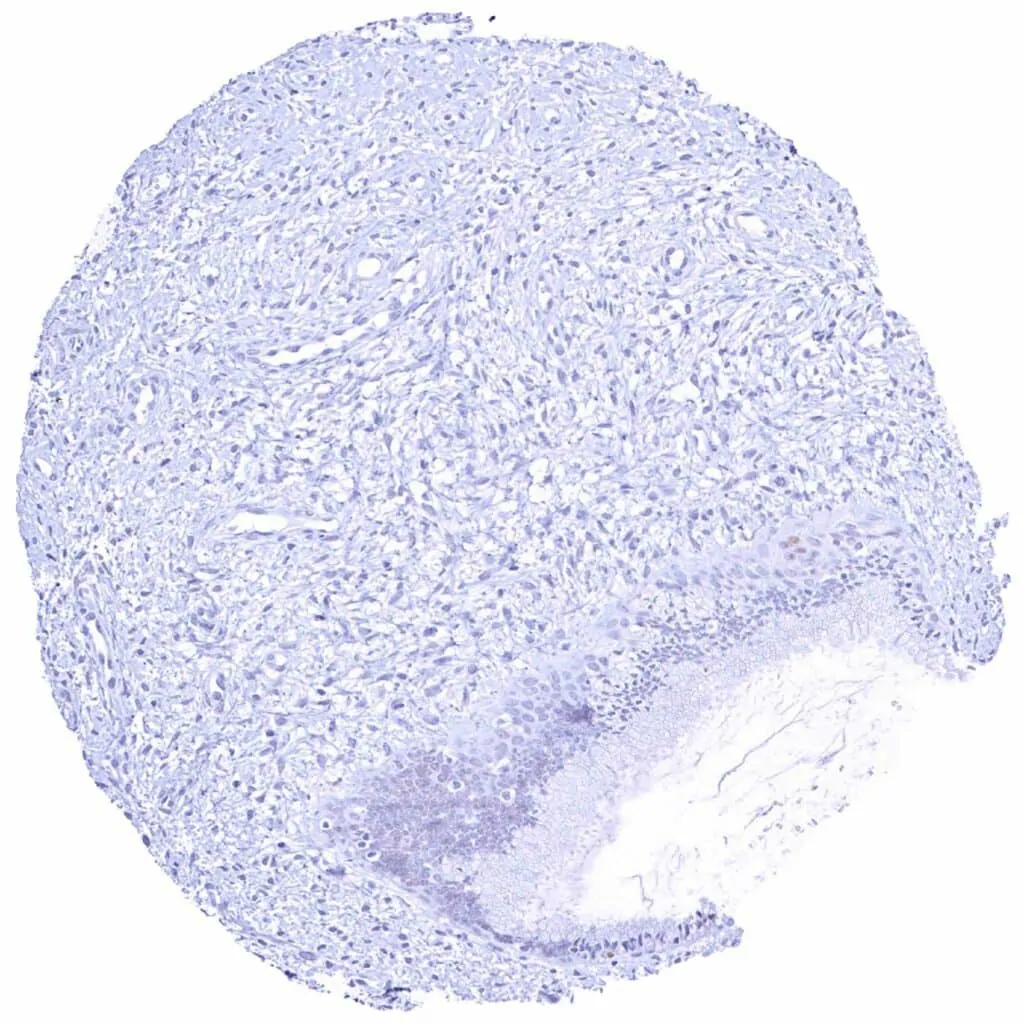

Sinus paranasales – Weak to moderate Cyclin E1 staining of a subset of inflammatory cells